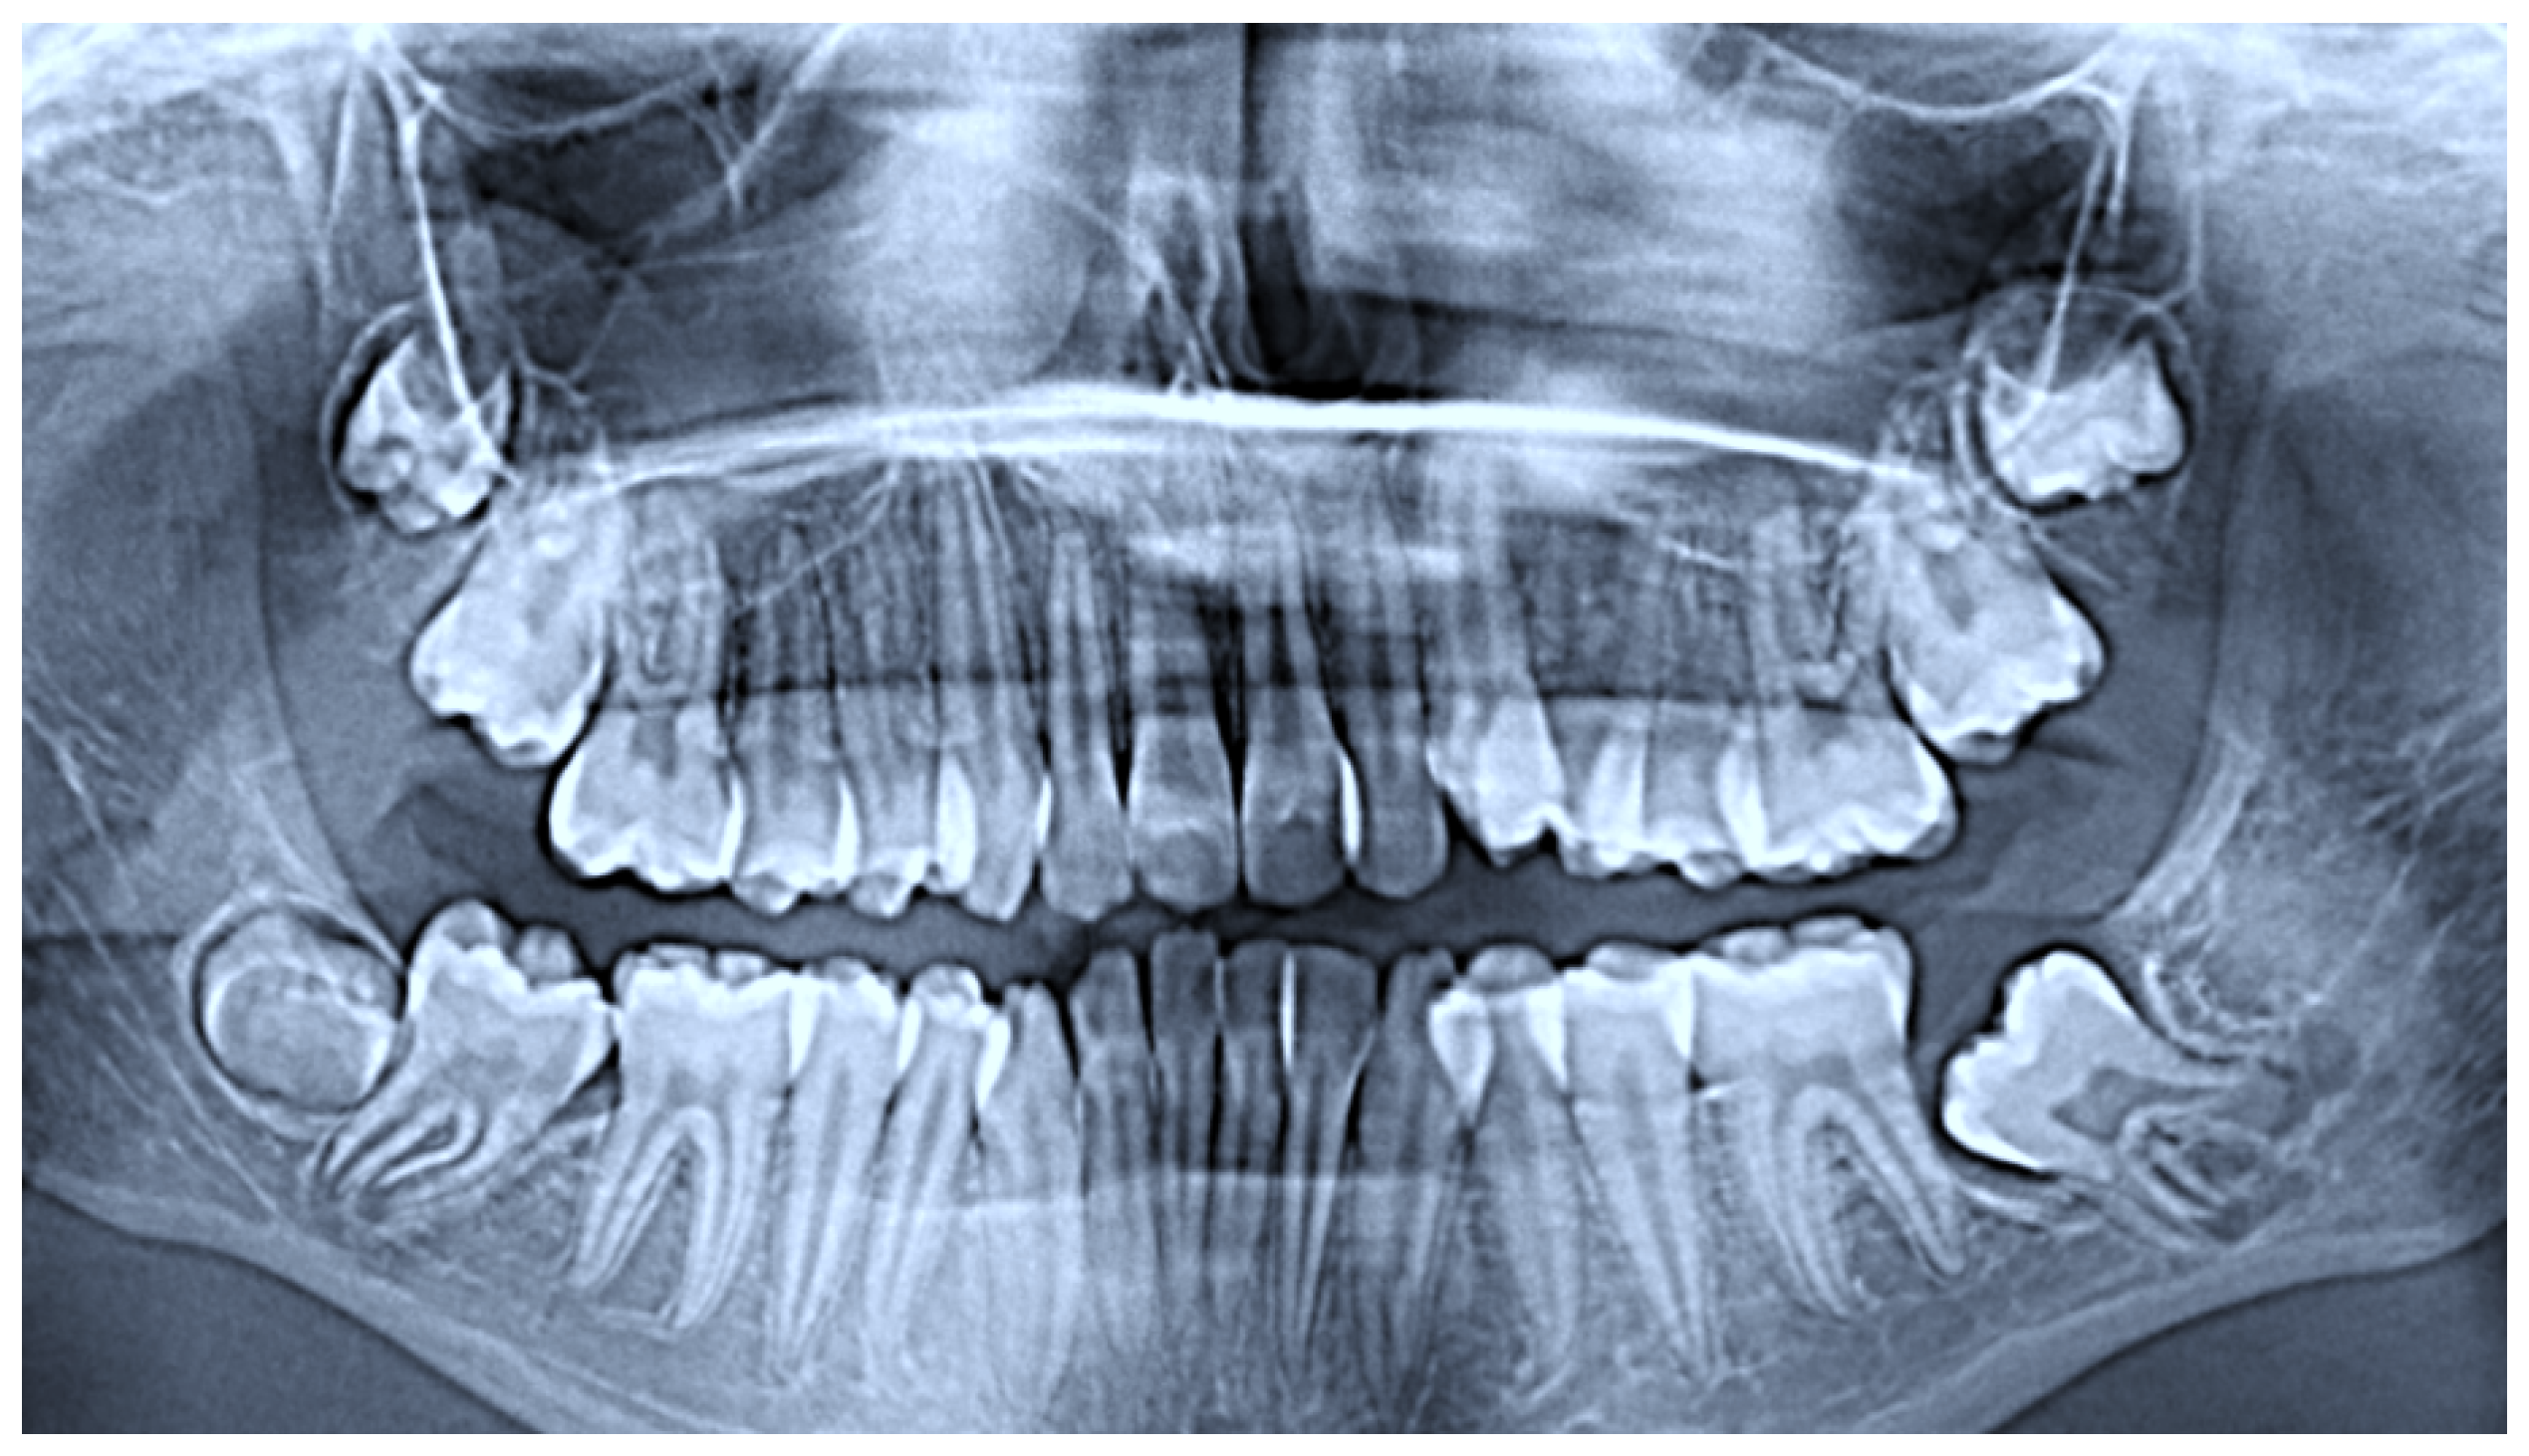

2.1. Case Presentation